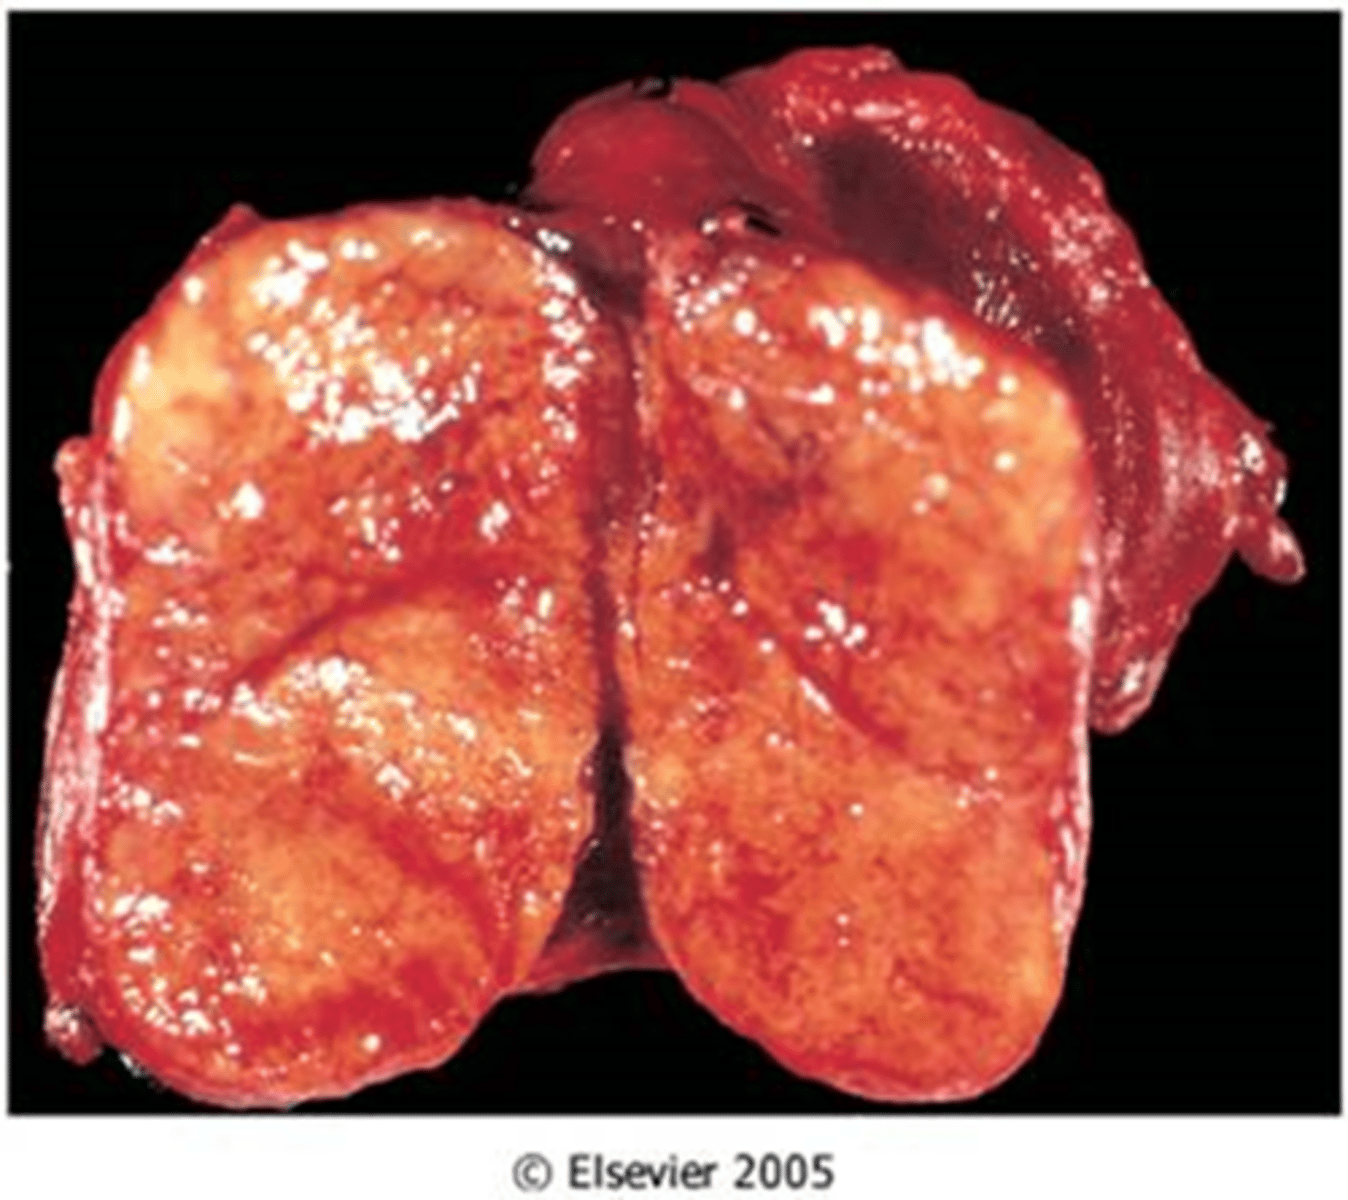

Adrenal Hyperplasia

Identify the pathology